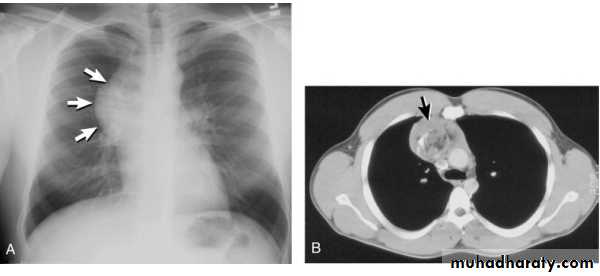

Tension pneumothorax.

On a posteroanterior chest x-ray (A), the left hemithorax is very dark or lucent because the left lung has collapsed completely (white arrows).

The tension pneumothorax can be identified because the mediastinal contents, including the heart, are shifted toward the right, and the left hemidiaphragm is flattened and depressed. A computed tomography scan done on a different patient with a tension pneumothorax (B) shows a completely collapsed right lung (arrows) and shift of the mediastinal contents to the left.